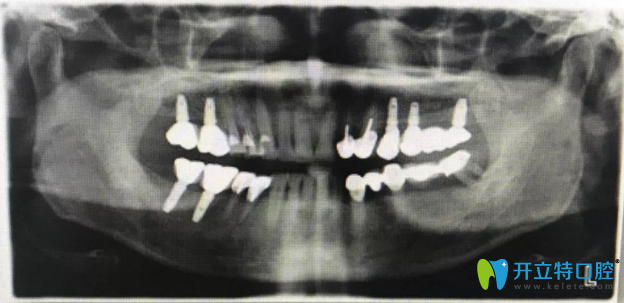

真人案例:能夠代替真牙使用的種植牙在X光片下是這樣子

莫先生今年39歲,莫先生今年39歲,卻因為嚴重的牙周病,導(dǎo)致全口牙松動,而且牙齒缺失還很嚴重,年在重慶牙博士口腔一眼咨詢之后,考慮了很久,他終于下定決定來牙博士做種植牙手術(shù)啦